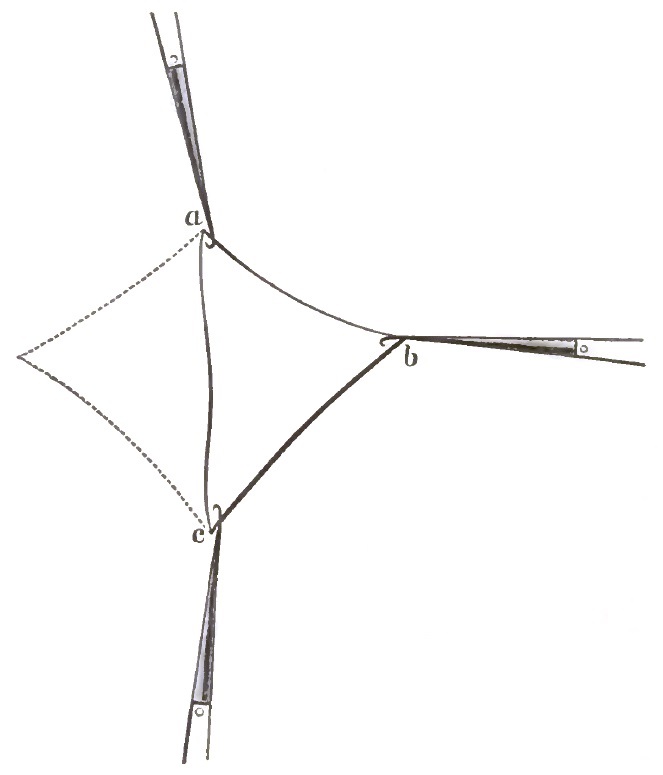

| 9. | THE FIRST SUTURE BEFORE TWISTING IN EMMET'S OPERATION IN PROCIDENTIA |

| 10. | FOLDS ON THE ANTERIOR VAGINAL WALL FORMED AFTER TWISTING THE FIRST SUTURE |

| 11. | EMMET'S OPERATION FOR PROCIDENTIA AND URETHROCELE COMPLETED |

| 12. | DIAGRAM OF EMMET'S OPERATION |